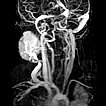

Das Mädchen ist jetzt 24 Monate alt, die Raumforderung hat sich nicht zurückgebildet. Sie ist deutlich sichtbar und bereitet der Patientin klaren Druckschmerz. Die MIP einer dynamischen, kontrastmittelunterstützten MR-Angiographie zeigt die starke Anreicherung des Hämangioms, das immer noch ausgedehnt ist. Die hauptsächliche venöse Drainage läuft über die Vena jugularis externa, im proximalen Bereich zeigt sich hier eine massive Stenose des Abstroms.